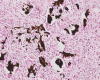

グラム チール・ネルゼン グロコット ワルチン・

スターリー法

グラム染色(グラム陽性菌)の染色態度 チール・ネルゼン染色(抗酸菌)の染色態度 グロコット染色(真菌)の染色態度 ワルチン・スターリー法(ピロリ菌)の染色態度